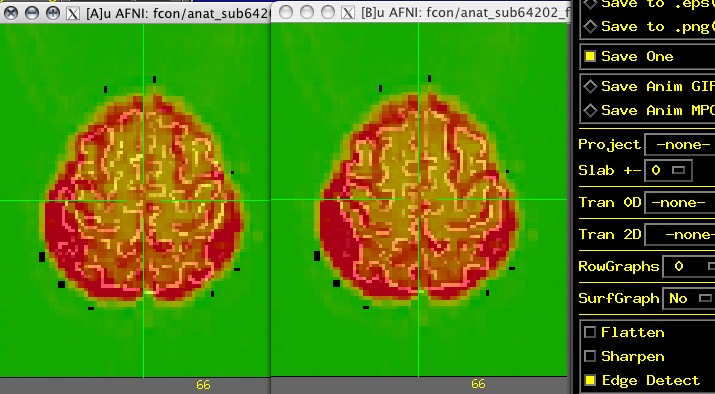

Regarding the flipping of 64202 and 81737, I think Brad may be

right. I am using basically the same methodology as him, so that

might be expected. For visualization, it is helpful to look at

edges within the images. Attached is an image of 64202 as received

and left-right flipped antomical dataset and both aligned to the

EPI data, as Brad suggested. For AFNI users, the edges can be seen

in the underlay (background anatomical) dataset by using the

Display control panel, edge detect option and even better with the

@AddEdge script or the -AddEdge option to align_epi_anat.py.

Sometimes the left-right flipping is more obvious, as with major asymmetric differences in ventricle sizes. Here it's much more subtle (it's really kind of amazing Brad saw this at all). By looking at some of the more superior slices, it becomes more obvious the sulcal edges do not align well while the flipped volume does align well at those edges.